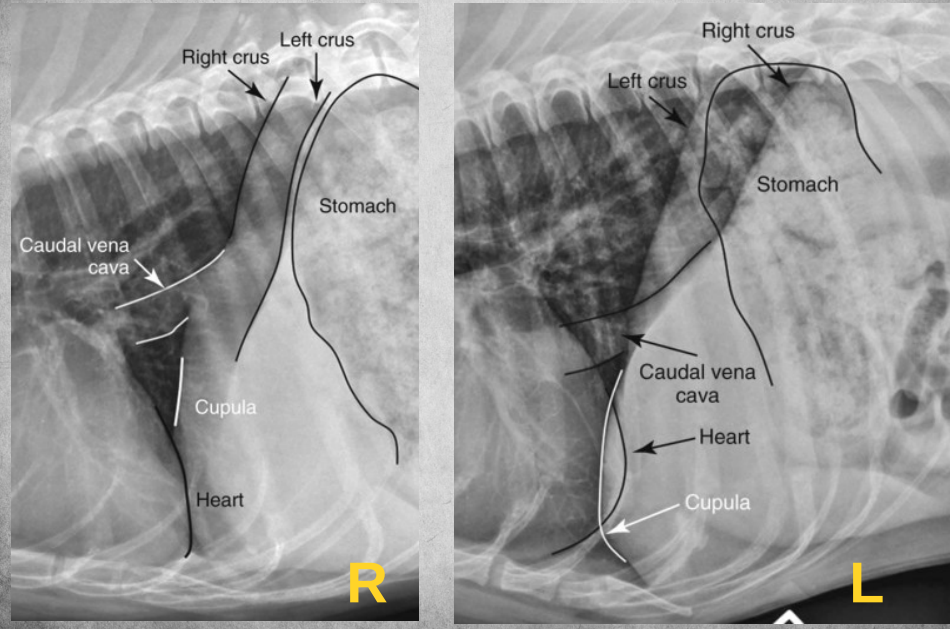

Differences between Right and left lateral thorax views:

A

In right lateral:

the diaphragmatic crura are parallel (in left, they form a V)

in right lateral, the caudal vena cava merges with the cranially positioned crus and with the caudal when its left lateral

left lung is seen better in right lateral

heart more egg-shaped in right lateral, rounder in left.

In left lateral: blood vessels of cranial lobes are easier to differentiate.

thoracic lymph nodes may be seen in right lateral but rarely ever in left lateral.